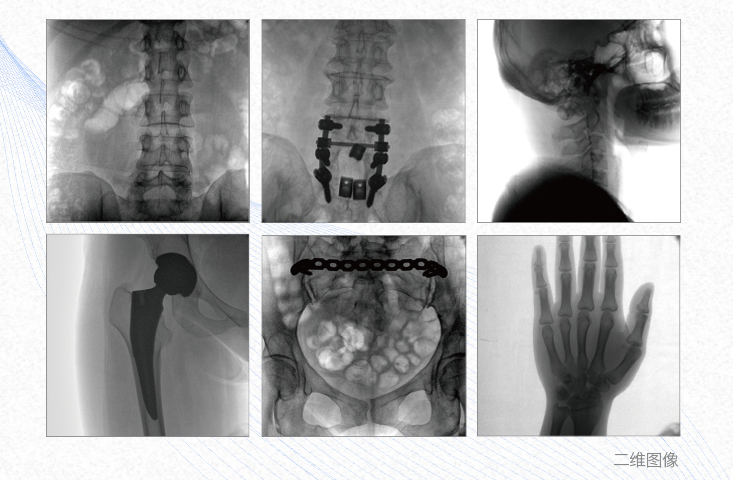

1、脊柱外科

有效重建復雜的脊柱三維模型,提供準確的二維、三維圖像,提高螺釘植入的準確性,縮短手術(shù)時(shí)間,減少并發(fā)癥的概率,降低輻射的攝入。

2、創(chuàng )傷外科

例如骨盆骨折內固定術(shù),可術(shù)中三維重建髖臼關(guān)節面,準確定位并植入螺釘,有效縮短螺釘植入的時(shí)間和透視暴露時(shí)間,減少術(shù)中及術(shù)后并發(fā)癥發(fā)生的概率。

3、關(guān)節外科

主要應用于肩關(guān)節、肘關(guān)節、髖關(guān)節、膝關(guān)節的關(guān)節置換及解剖復位的定位。它可以準確地置入假體,減少輻射時(shí)間,降低輻射劑量。

4、截骨矯形外科

例如治療先天性脊柱側后凸畸形,可有效引導術(shù)者植入后路螺釘并切除半錐體,達到滿(mǎn)意的截骨矯正效果。